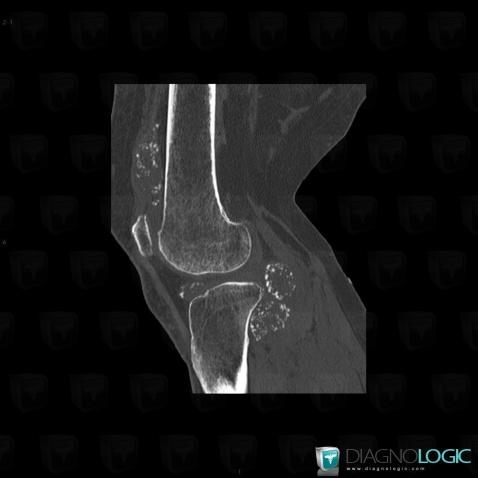

Ostéochondromatose synoviale, Fémur -inférieur, Tibia -supérieur, Scanner

- Diagnostic Ostéochondromatose synoviale, Localisation(s) Fémur - 1/3 inférieur, comportant les gammes Ostéolyse corticale, Erosion corticaleTibia - 1/3 supérieur, comportant les gammes Ostéolyse corticale, Erosion corticaleAutres parties molles/nerfs - Genou, comportant les gammes Calcifications des parties molles, Masse des parties molles avec ostéolyse, Masse calcifiée des parties molles, Masse des parties molles juxta articulaires